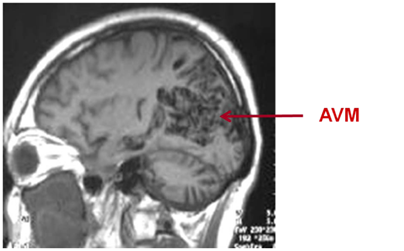

AVMs consist of abnormal collection of arteries and veins. They are the most common cause of haemorrhagic stroke in children and young adults. Radiosurgery is the treatment option recommended for lesions less than 3cm in diameter and located in eloquent areas where surgery can cause neurological deficits. This study aims to identify endothelial protein targets of AVMs that are differentially expressed compared to normal vessels post radiosurgery, to develop a ligand directed vascular treatment that promotes rapid thrombosis in AVM vessels. This is the first time that proteomics approach has been used in AVMs study (Figure 1).

Figure 1